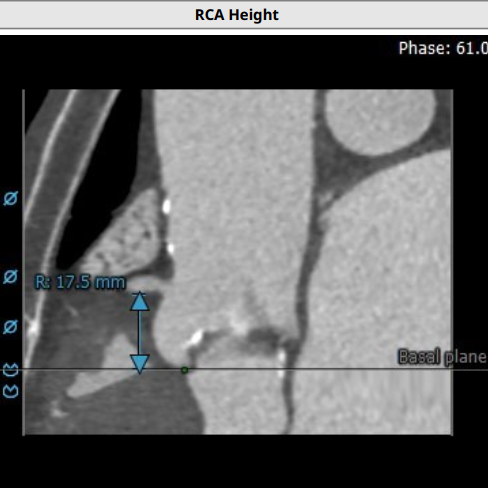

超声心动图显示,主动脉最大流速482cm/s,最大压差93mmHg,平均压差50mmHg,LVEF65%。CT显示主动脉瓣为TYPE2型二叶瓣,严重钙化,右无、左无可见粘连伴钙化,瓣环平面可见钙化,钙化延伸至流出道及二尖瓣前叶根部,左冠高度约12mm,瓣叶长度14.9mm,存在一定左冠风险,法式窦平均直径33.7mm,STJ高度约21.8mm、直径约30.2mm。